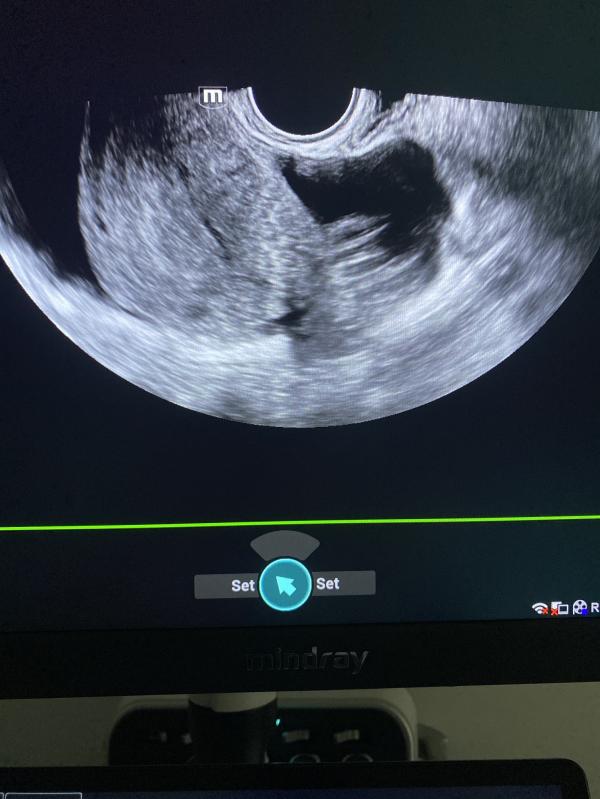

За счёт разрыва кисты и наличия жидкости в малом тазу видем на : первом фото спайка;